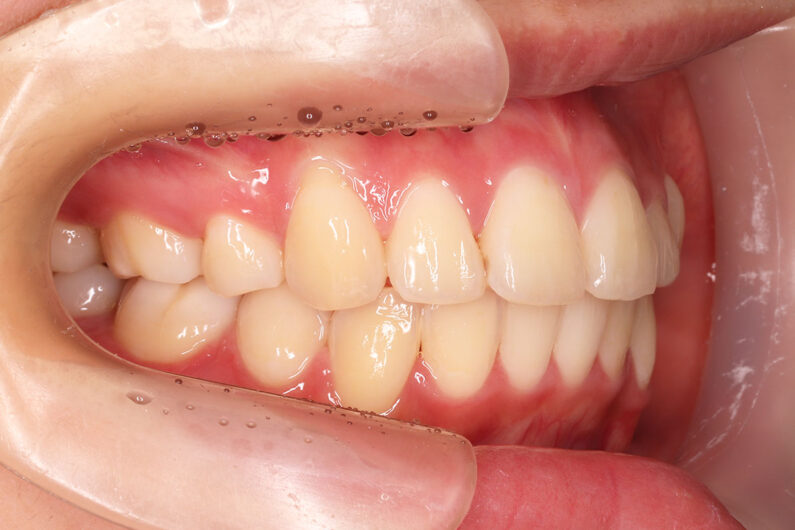

マルチブラケット 動的治療期間 3年5か月 調整回数29回

治療後は前歯は後退し、前歯の傾斜度も良くなっています。 口唇の緊張感も改善し、エステティックラインも綺麗になりました。